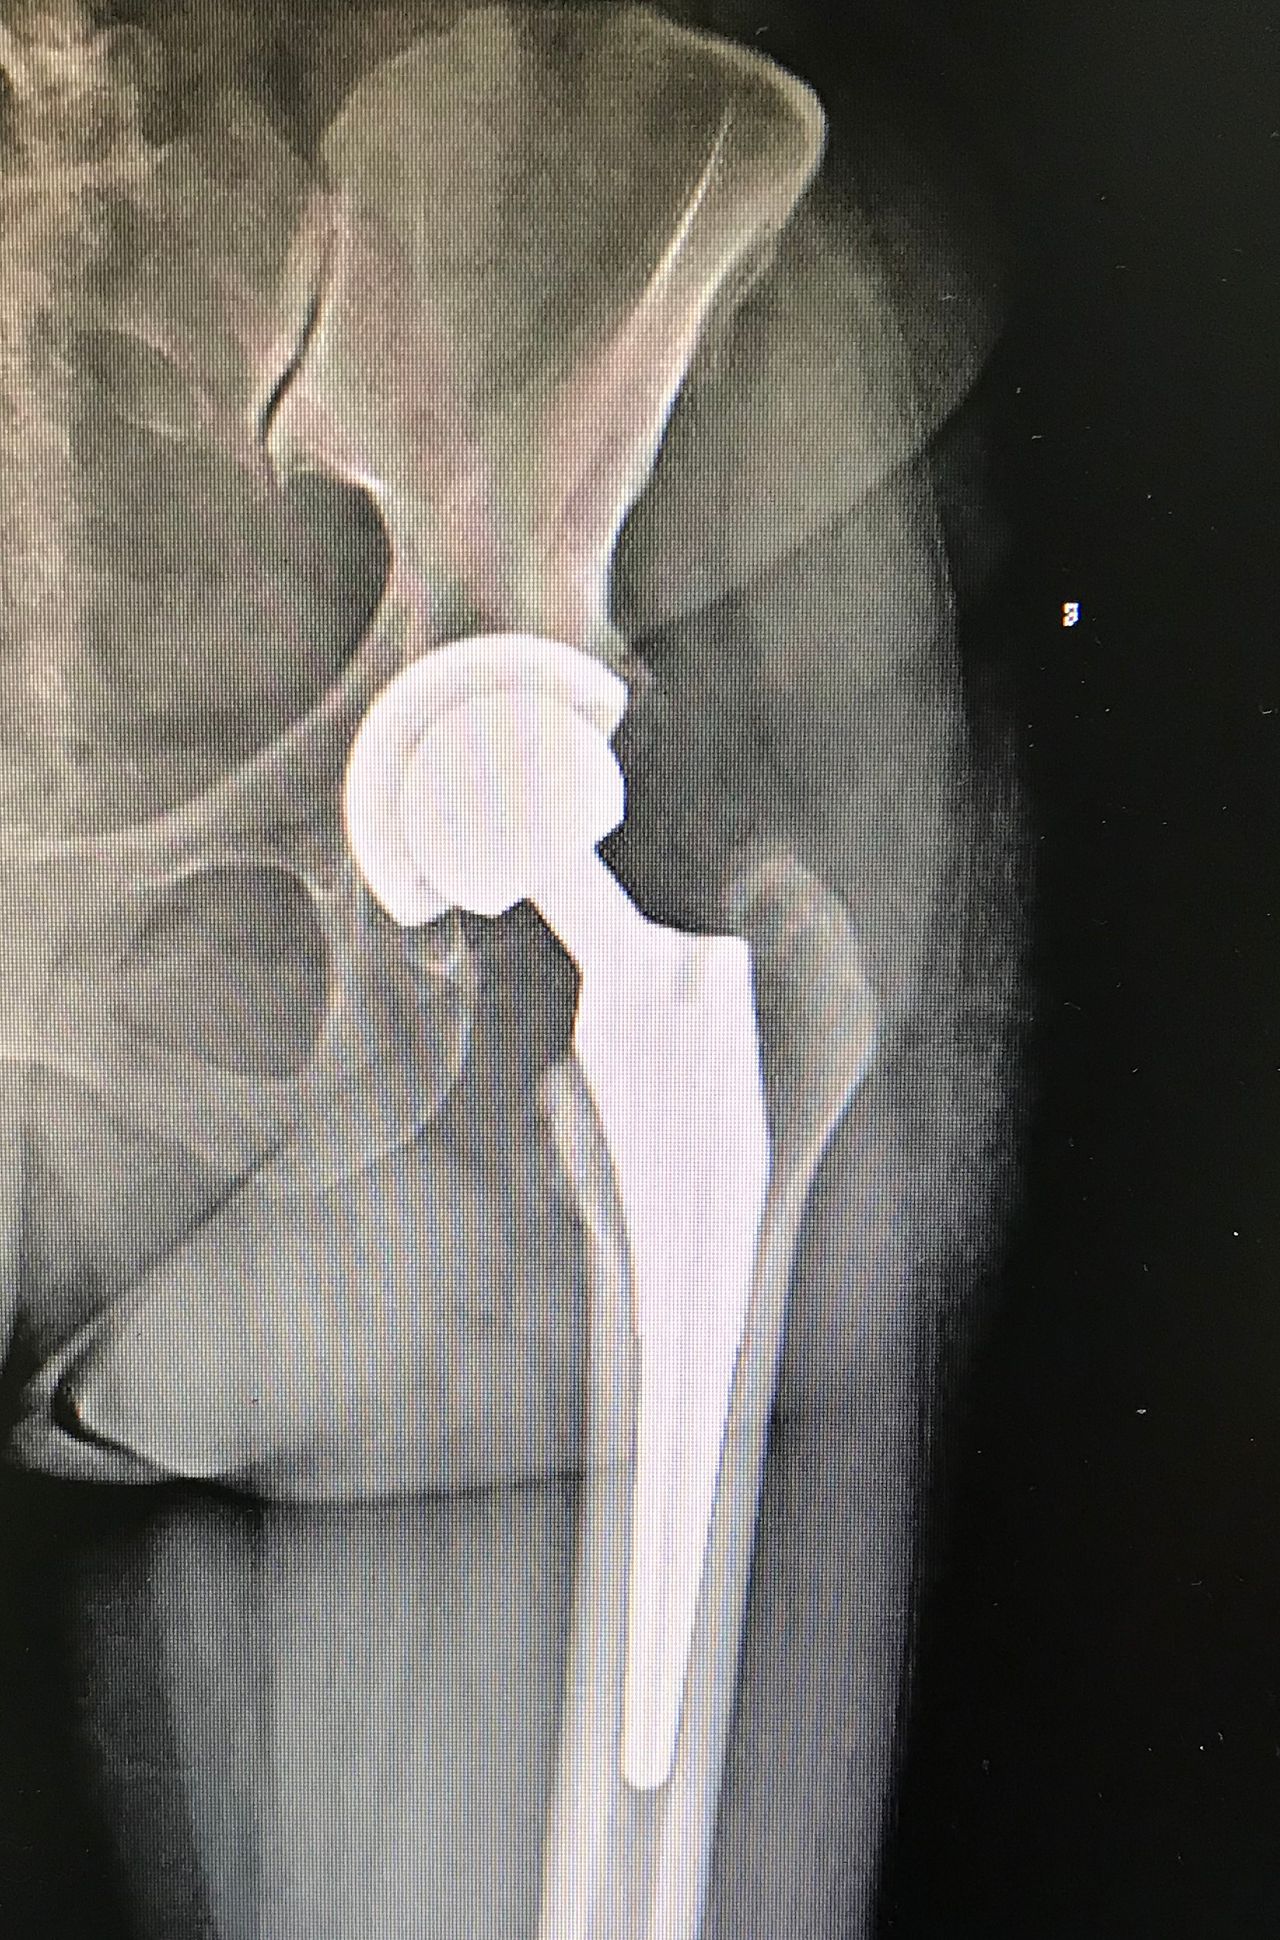

La protesi d’anca

• Ortopedia dell'anca